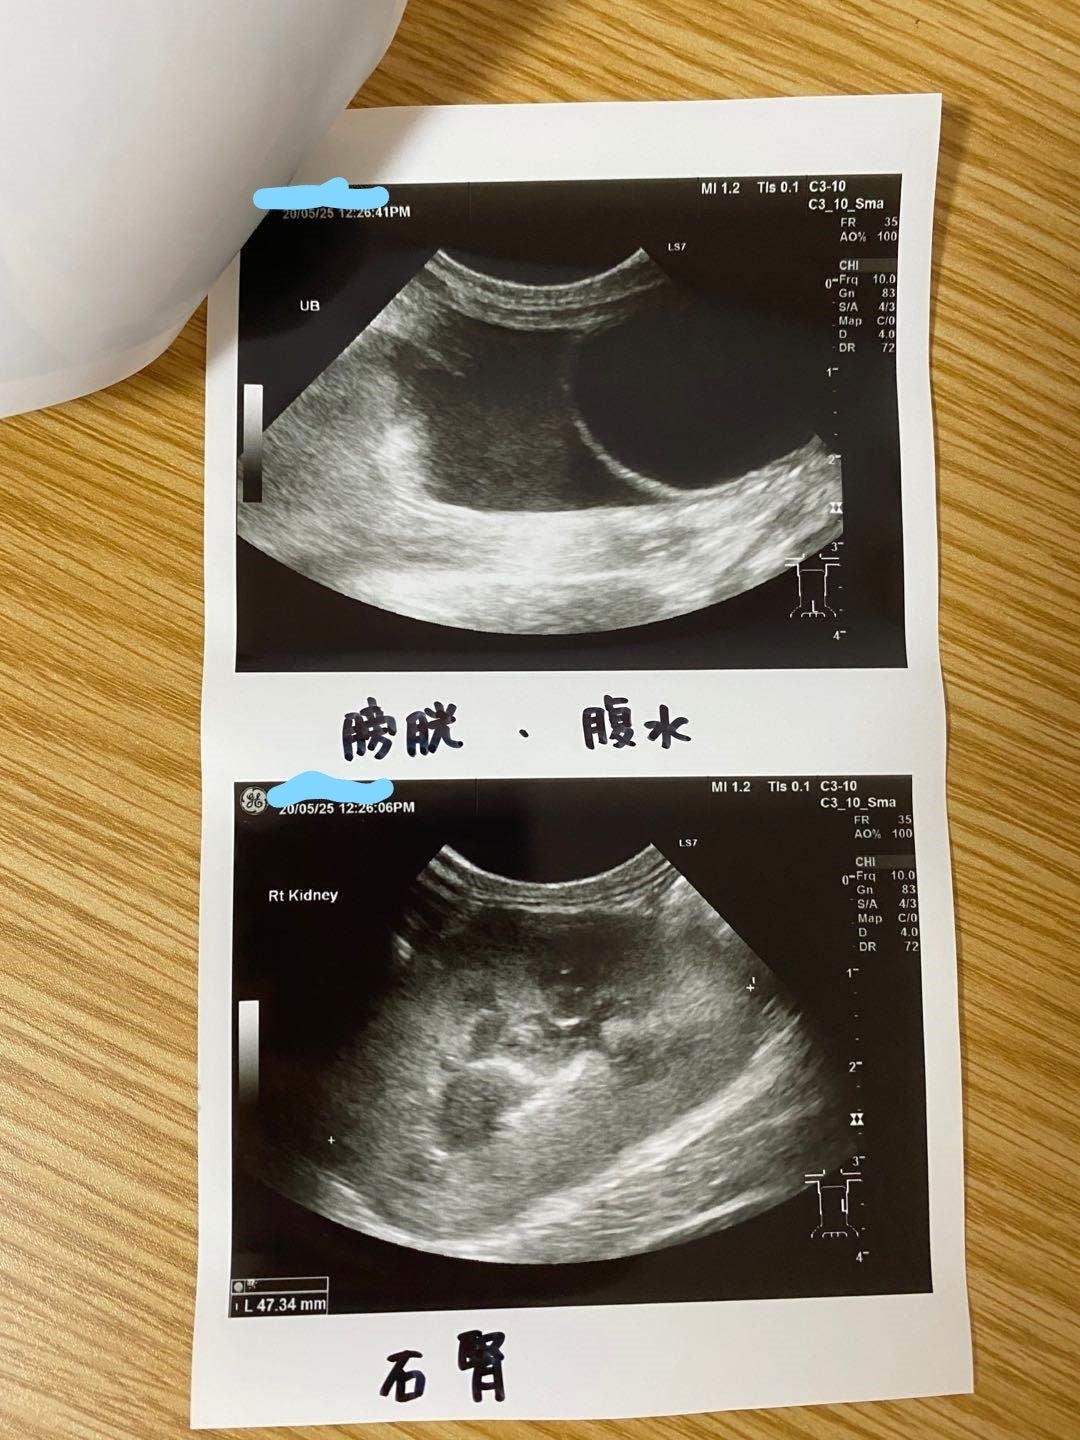

中秋ちゃんが今月の22日に猫伝染性腹膜炎(以下FIP)に発症しました。胸と腹は水が溜まって、肝臓が肉芽腫があります。この病気は発症すると、個体差によって数日から数か月しか生きれません。その日から中秋ちゃんが元気なく何も食べずになりました。23日いつもお世話になる動物病院に言って、FIPが発症と言われました。病院の方はステロイドと痛み止めを使ってできるだけ楽してしかできません。安楽死も方法の一つと言われた。

5/25家の近くの協力病院に行って、痛く辛い検査をして、中期混合型と診断されました。

腹水がたまっています

肉芽腫が見つかります

39℃の熱と重度の貧血もあります

強い炎症もあります